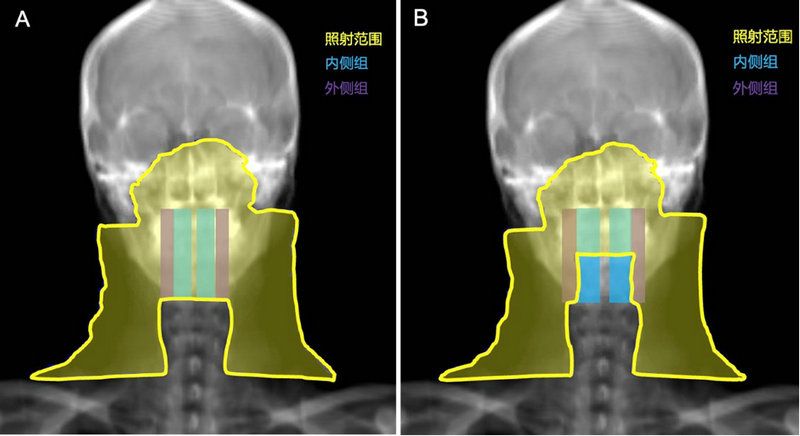

鼻咽癌預防照射范圍示意圖

A對照組:內、外側組咽后淋巴結區均接受預防照射(左)

B試驗組:內側組咽后淋巴結區豁免預防照射(右)